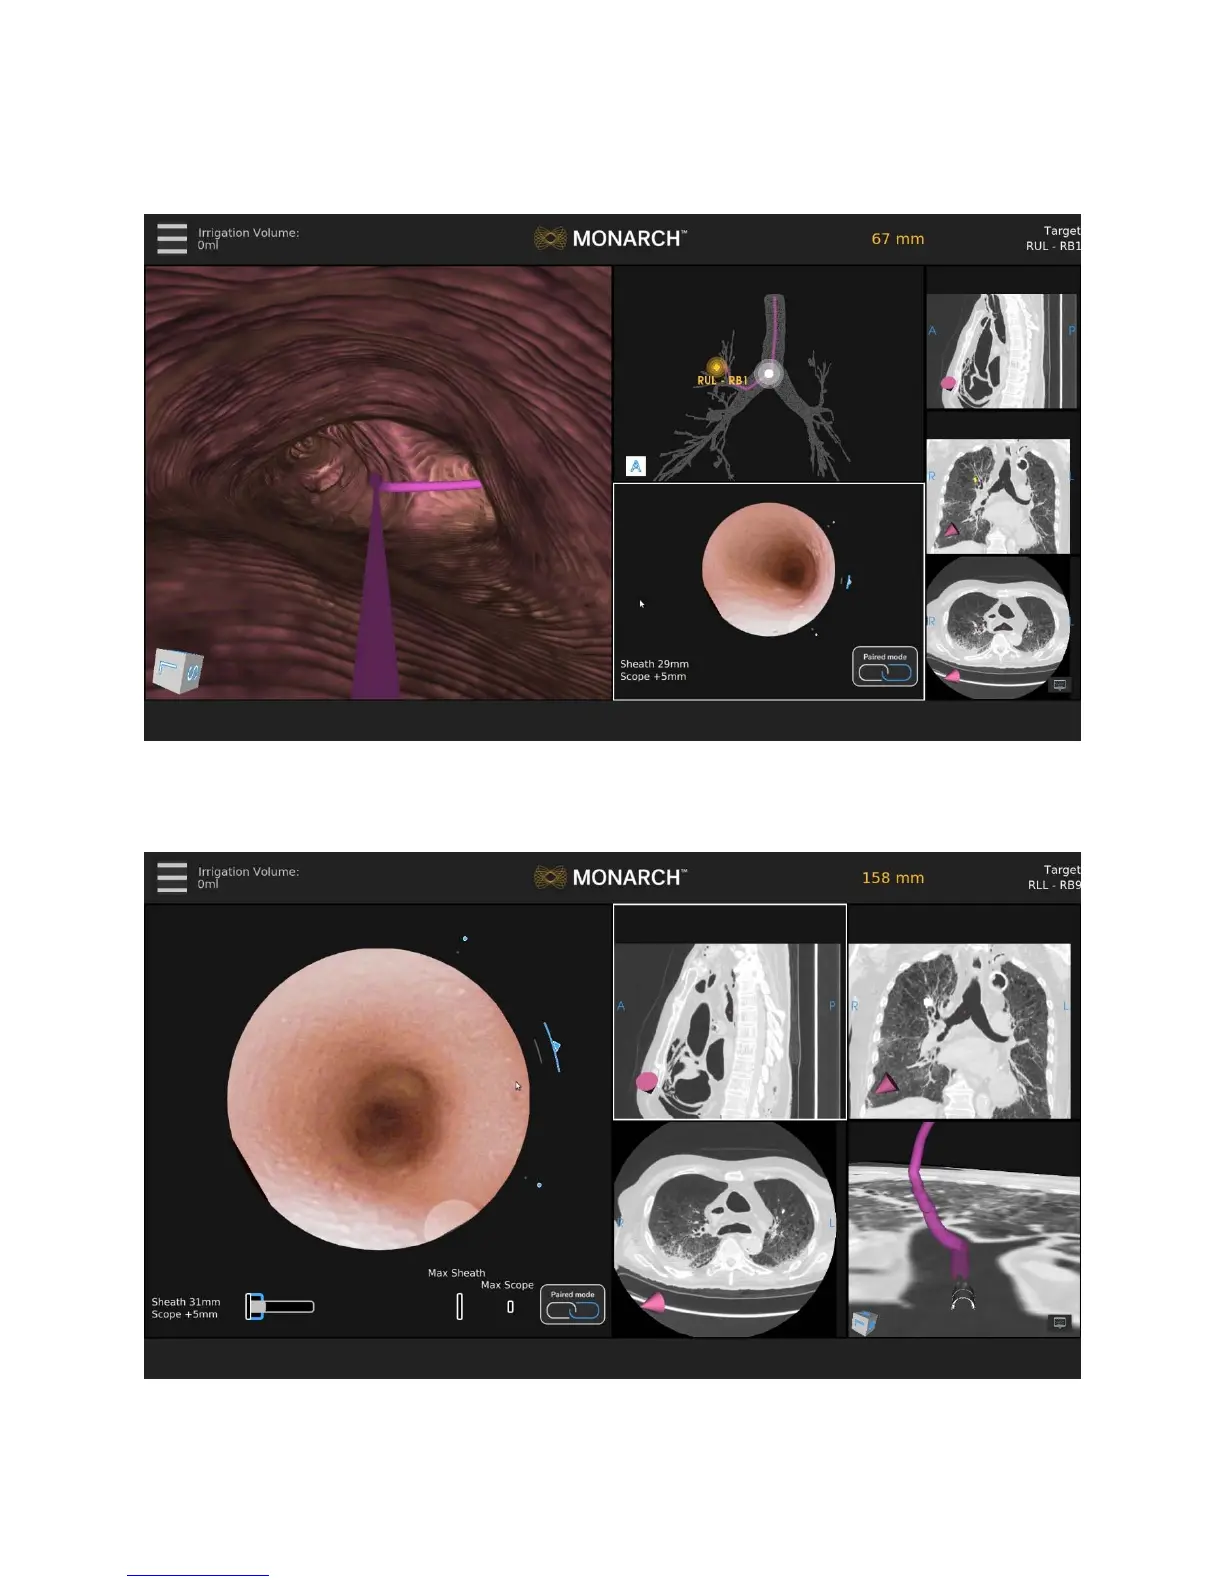

Use the Scrolling Area to select among different views. Once you select a view,

it’s promoted to Primary Area.

If you select one of the CT views, the screen transitions to a CT-centric view as

described above.